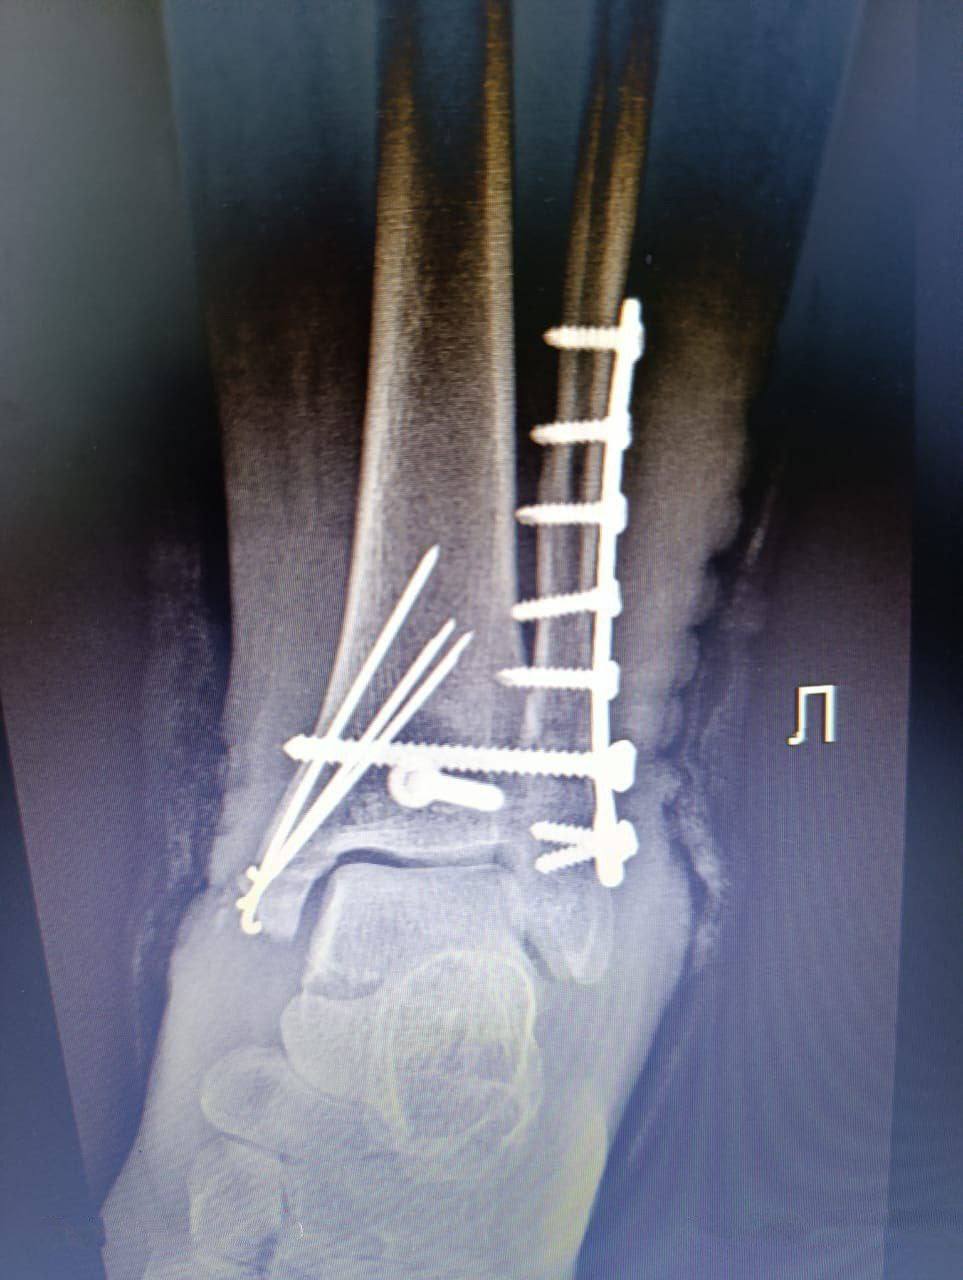

Сюжет знакомый: ирбитчанка шла по улице, споткнулась, упала и получила травму. Теперь у неё металлические спицы и шуруп в лодыжке.

Три месяца реабилитации, восстановительные процедуры и физиотерапия помогли женщине вновь двигаться и работать.